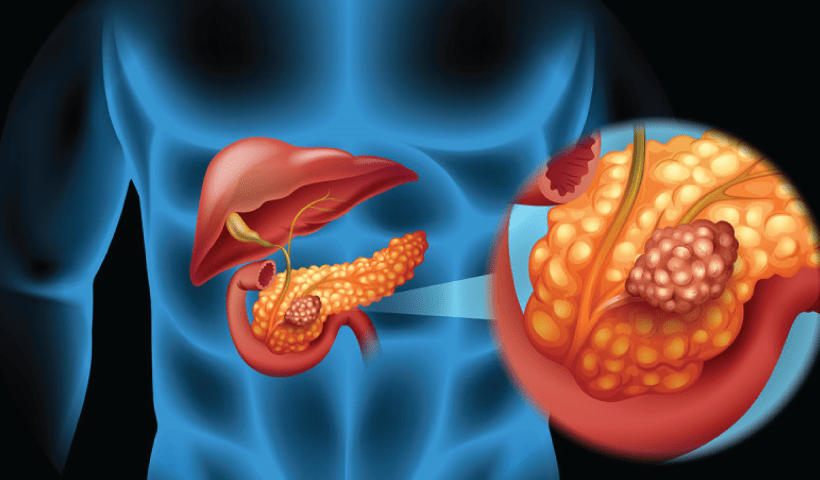

View More IIT Kanpur Explores India’s Digital Public Infrastructure in Campus DialogueIIT Madras to Develop Biomarkers for Early Detection of Pancreatic Cancer

The Indian Institute of Technology (IIT), Madras has established a first-of-its-kind Centre of Excellence that is undertaking research to develop biomarkers for early detection of…